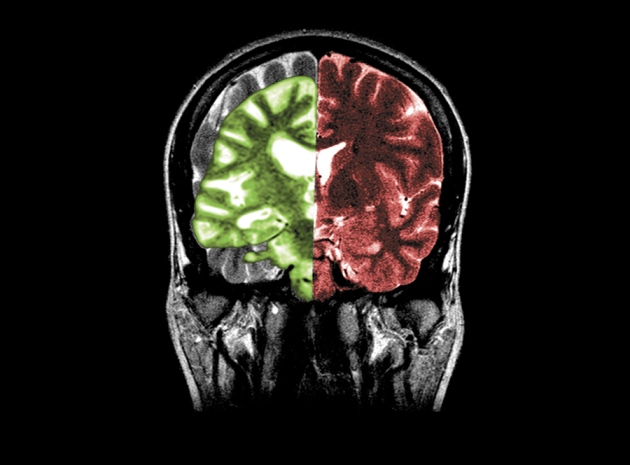

图片来源:Medical Body Scans/Jessica Wilson/SPL